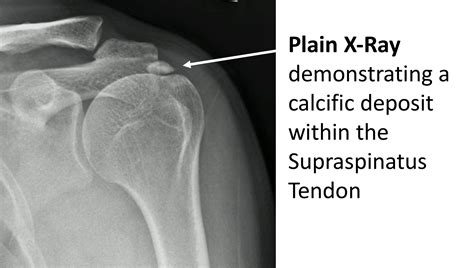

Calcification tendonitis, also known as calcific tendinitis, occurs when calcium deposits form within the tendons, most commonly in the rotator cuff tendons of the shoulder. These deposits can cause inflammation, pain, and restricted movement. The condition can be acute or chronic, and its severity can vary widely among individuals.

Diagnosing calcification tendonitis involves a combination of physical examination and imaging tests. The diagnostic process typically includes:

• Physical examination: A healthcare provider will assess the range of motion, strength, and tenderness in the affected area.

• Imaging tests: X-rays, ultrasound, or MRI scans can help visualize the calcium deposits and assess the extent of the damage.